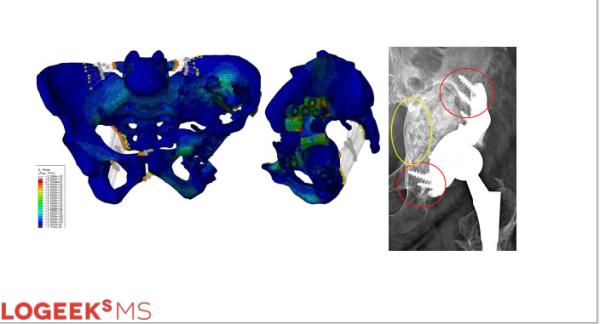

Определение объемов остеопластики с целью минимизации размеров индивидуального имплантата

Определение объемов остеопластики из головки бедренной кости

Ревизионное эндопротезирование как технология

Использование математического моделирования в разработке имплантатов позволяет использовать необходимый минимум металла и максимум остео-пластики, а также определить «слабые места» и запланировать максимальную фиксацию винтами.